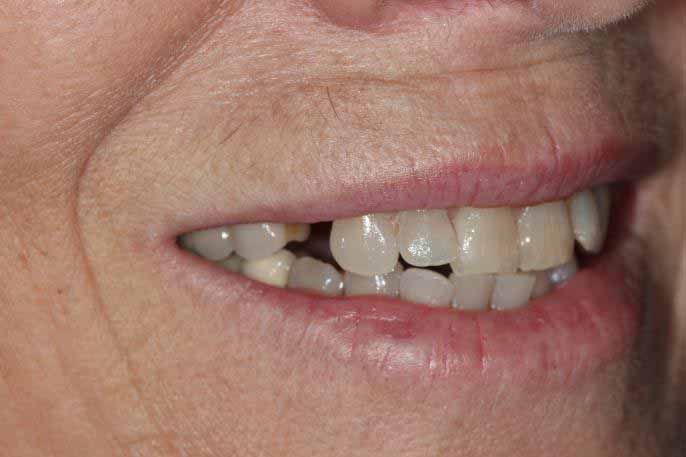

Same Day All on 4 Dental Implants Treatment

This patient had missing teeth and the those that remained were failing. After discussing with the patient, it was decided to remove the failing teeth and rehabilitate with same day all on 4 dental implants.

This treatment is usually carried out in 1 day (after a few preparatory appointments for moulds, x-rays, etc). The failing teeth were removed and implants place on the same day, with a temporary bridge (fixed teeth) attached also on the same day. Following a period of 3 to 6 months, moulds were taken and the definitive bridge placed